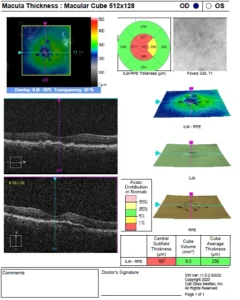

- OPTICAL COHERENCE TOMOGRAPHY (OCT)

OCT showing normal foveal contour in both eyes

Optical coherence tomography is a non-invasive imaging test, which uses light waves to take cross-section pictures of patients’ retina.

With OCT, the retina specialist can see each of the retina’s distinctive layers. This allows mapping and measuring retinal thickness. These measurements help with diagnosis. OCT also guides treatment for retinal diseases, like age-related macular degeneration (AMD), diabetic eye disease, and macular oedema.

OCT is often used to evaluate disorders of the optic nerve as well. The OCT exam helps the retina specialist see changes to the fibres of the optic nerve. For example, it can detect changes caused by glaucoma.